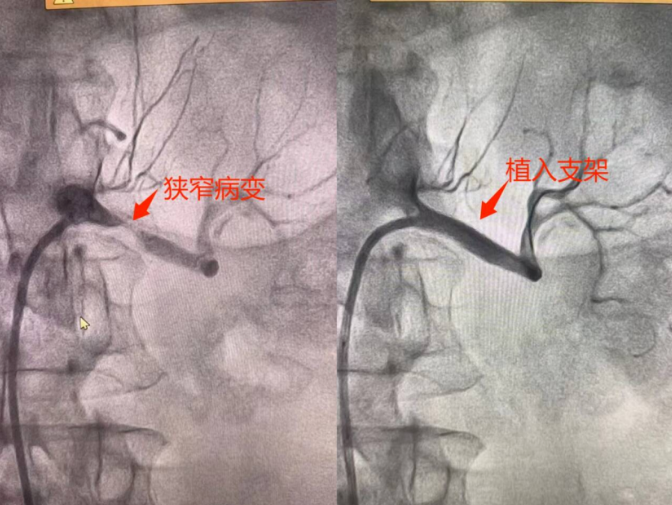

微創(chuàng)介入,立竿見(jiàn)影為有效控制血壓,避免腎功能進(jìn)一步受損,心血管內(nèi)科團(tuán)隊(duì)為患者制定了詳細(xì)的治療方案,行冠狀動(dòng)脈造影同時(shí)行腎動(dòng)脈造影檢查進(jìn)一步明確患者冠脈及腎動(dòng)脈血管情況,根據(jù)冠脈造影結(jié)果給予冠狀動(dòng)脈支架植入術(shù),根據(jù)腎動(dòng)脈造影結(jié)果給予患者行左腎動(dòng)脈支架植入術(shù)。在介入導(dǎo)管室的配合下,手術(shù)團(tuán)隊(duì)通過(guò)微創(chuàng)介入技術(shù),成功為患者同時(shí)植入了腎動(dòng)脈支架及冠脈支架,恢復(fù)了冠狀動(dòng)脈及腎動(dòng)脈的正常血流。術(shù)后,患者血壓迅速下降,胸痛癥狀明顯緩解,術(shù)后血壓穩(wěn)定在正常范圍,患者恢復(fù)良好。